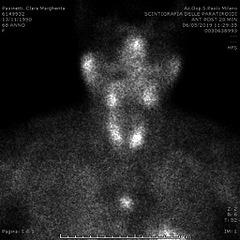

We report the case of a woman with primary hyperparathyroidism suspected of mediastinal ectopic parathyroid adenoma revealed to be a thymoma. Our aim was to focus on some possible criticisms in distinguishing between ectopic parathyroid and thymus.

我们报告了一例原发性甲状旁腺功能亢进症女性患者,怀疑为纵隔异位甲状旁腺腺瘤,结果发现是胸腺瘤。我们的目的是关注在区分异位甲状旁腺和胸腺时可能存在的一些争议点。